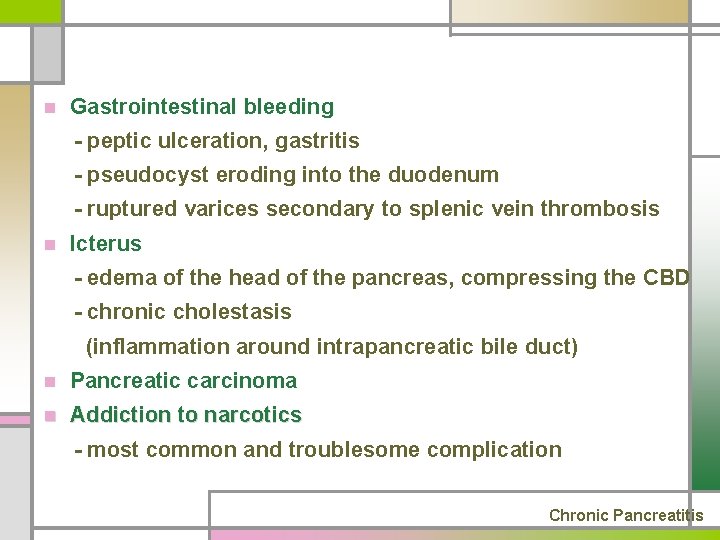

n Gastrointestinal bleeding - peptic ulceration, gastritis - pseudocyst eroding into the duodenum - ruptured varices secondary to splenic vein thrombosis n Icterus - edema of the head of the pancreas, compressing the CBD - chronic cholestasis (inflammation around intrapancreatic bile duct) n Pancreatic carcinoma n Addiction to narcotics - most common and troublesome complication Chronic Pancreatitis